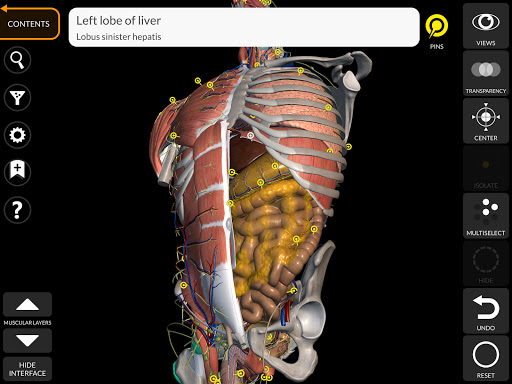

"Anatomy 3D Atlas" memungkinkan Anda mempelajari anatomi manusia dengan cara yang mudah dan interaktif.

Melalui antarmuka yang sederhana dan intuitif, Anda dapat mengamati setiap struktur anatomi dari sudut mana pun.

Model 3D anatomi sangat terperinci dan memiliki tekstur hingga resolusi 4k.

Pembagian berdasarkan wilayah dan tampilan yang telah ditetapkan sebelumnya memudahkan pengamatan dan studi bagian tunggal atau kelompok sistem dan hubungan antara organ yang berbeda.

MODEL ANATOMI 3D

saraf • Sistem pernapasan • Sistem pencernaan • Sistem urogenital (pria dan wanita) • Sistem endokrin • Sistem limfatik • Sistem mata dan telinga FITUR • Antarmuka yang sederhana dan intuitif • Putar dan perbesar setiap model dalam ruang 3D • Opsi untuk menyembunyikan atau mengisolasi satu atau beberapa model yang dipilih • Filter untuk menyembunyikan atau menampilkan setiap sistem • Fungsi pencarian untuk menemukan setiap bagian anatomi dengan mudah • Fungsi penanda untuk menyimpan tampilan khusus • Rotasi cerdas yang menggerakkan pusat rotasi secara otomatis • Fungsi transparansi • Visualisasi otot melalui tingkat lapisan dari yang superfisial hingga yang terdalam • Dengan memilih model atau pin, istilah anatomi terkait akan muncul • Deskripsi otot: asal, • Tampilkan/ Sembunyikan antarmuka UI (sangat berguna dengan layar kecil) MULTIBAHASA • Istilah anatomi dan antarmuka pengguna tersedia dalam 11 bahasa: Latin, Inggris, Prancis, Jerman, Italia, Portugis, Turki, Rusia, Spanyol, Mandarin, Jepang, dan Korea • Istilah anatomi dapat ditampilkan dalam dua bahasa secara bersamaan PERSYARATAN SISTEM • Android 8.0 atau yang lebih baru, perangkat dengan RAM minimal 3GB Reversi